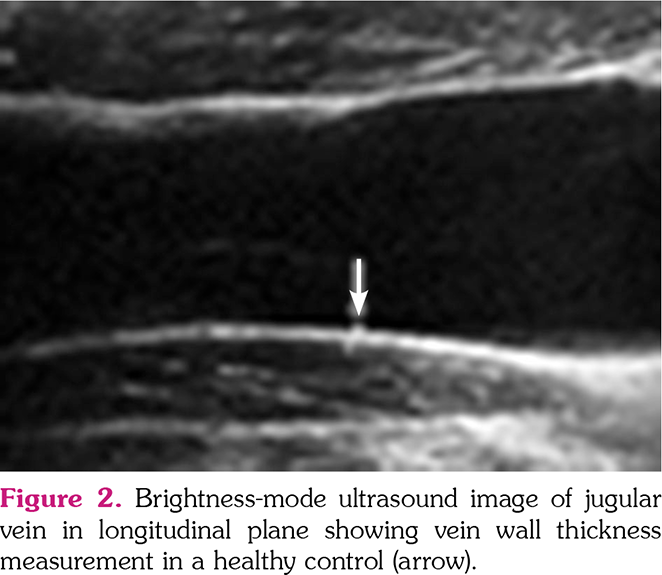

All US examinations were performed by an aboard-certified radiologist with seven years of experience in US imaging who was blinded to cases on the same day with clinical assessment. A second radiologist with an experience of three years in US imaging performed IMT and VWT measurements of the first 20 individuals on the same day with the first radiologist to evaluate the inter-observer agreement. All US examinations were performed after a fasting period of 6 h. Bilateral CIMT, jugular vein, and common femoral VWTs were measured using a 4-15-MHz ML6-15 linear transducer (Logiq E9, General Electric Company, Fairfield, CT, USA). mesenteric, The portal vein, inferior vena cava, superior renal, and splenic VWTs were measured using a 2-8-MHz 9L-D linear transducer (Logiq E9, General Electric Company, Fairfield, CT, USA). US examinations were performed with a high-resolution US system (LOGIQ E9; GE Healthcare, Wauwatosa, WI, USA). VWTs were evaluated during the Valsalva maneuver and IMT was measured during neutral breathing in the supine position. All veins were evaluated in both longitudinal and transverse planes. CIMT was automatically measured in a longitudinal axis using the Auto-IMT application (GE Healthcare, Wauwatosa, WI, USA). Three measurements were performed by the observers from each vessel and the average of these measurements for each vessel was noted (Figures 1-3).